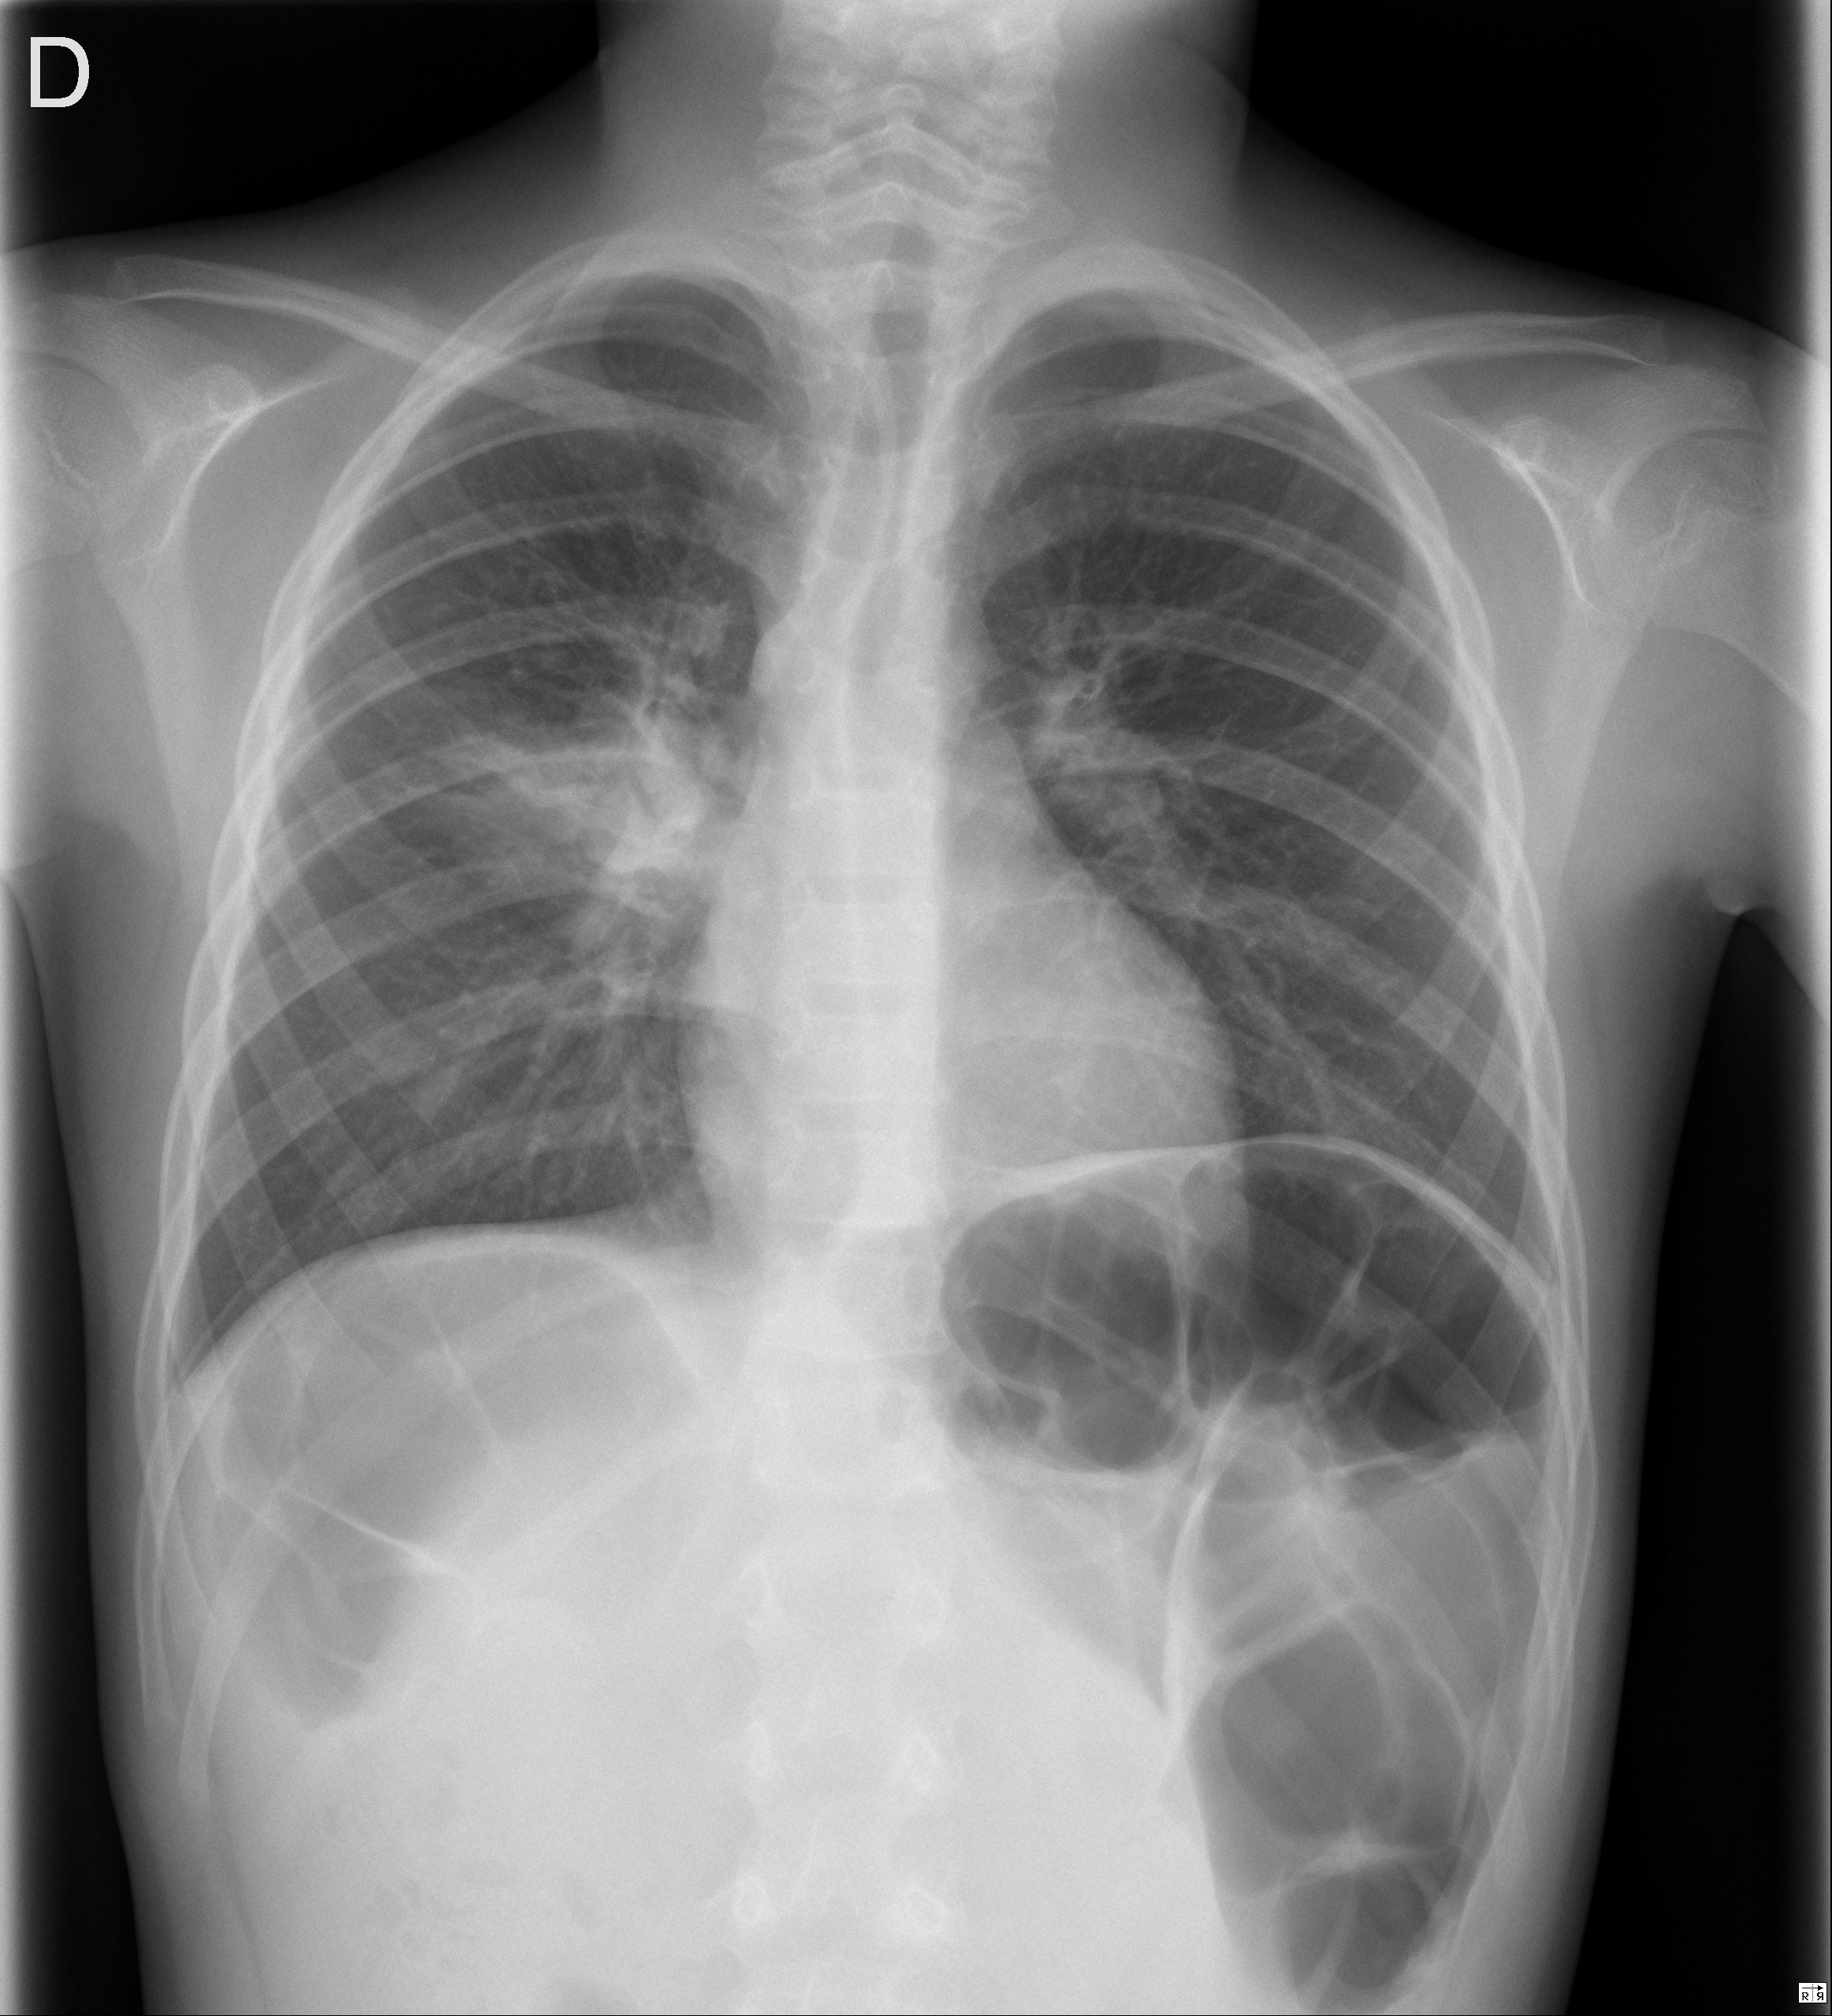

Niño de 9 años que acude a Urgencias por fiebre de hasta 38,9 °C de 72 horas de evolución asociada a tos productiva y mucosidad nasal. En la auscultación pulmonar se aprecian crepitantes en el campo superior derecho. El resto de la exploración física es normal. Se realiza radiografía de tórax posteroanterior, única proyección, que evidencia un aumento de la densidad en el campo pulmonar superior derecho, pero hay algo más (Figura 1).